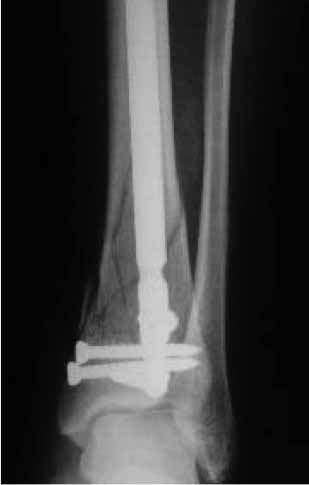

Уважаемые коллеги! Интересно ваше мнение по тактике лечения данной пациентки.Женщина 72 л соматически сохранная, умеренно полная, в мае прошлого года получила бытовую травму - открытый оскольчатый внутрисуставной перелом дистального метаэпифиза большеберцовой кости (Gustilo III-A) и поперечный перелом н/з малоберцовой кости со смещением отломков. Оперирована ургентно - открытая репозиция отломков малоберцовой кости, остеосинтез пластиной. ПХО раны голеностопного сустава, стабилизация отломков большеберцовой кости стержневым аппаратом. Репозиция отломков удовлетворительная (варус до 5 гр, рекурвация до 5 гр) - сильно за ней не гонялись, много осколков. В дальнейшем заживление ран первичное. Аппарат до 3 мес, затем гипсовая лонгета. Общий срок иммобилизации и разгрузки нижней конечности 4,5 мес - разрешена нагрузка после клинических и рентгенологических? признаков сращения. Последние 4 мес из поля зрения выпала, появилась сегодня. Беспокоят сильные боли при ходьбе, деформация голени, хромота. Р-контроль прилагается - варус 16 гр, рекурвация 35 гр (прошу прощения за качество снимков). Клинически варусно-рекурвационная деформация н/з голени, подвижность в н/з, боль. Движения в голеностопном суставе разгибание-сгибание 0/0/20. Трофика не нарушена, рубец области медиальной лодыжки плотный, спаян с подлежащими тканями. Больная хочет ходить без боли на ровной ноге (что вполне естественно). Возникает вопрос - как этого добиться? Удаление металлоконструкций, остеотомия малоберцовой на мой взгляд не обсуждаются - выполняются при любом из выбранных методов лечения (далее как мне видится в порядке предпочтения): - коррекция деформации аппаратом Илизарова с последующим БИОС ретроградным стержнем типа T2 AAN или аналогами (читал за и против данного метода, но по моему он единственный обеспечит больной раннюю нагрузку и стабильность пусть даже ценой потери ГСС (который и так уже потерян ИМХО) и ПТС). -коррекция деформации аппаратом Илизарова с оставлением этой фиксации как окончательной (необходимо ли выполнение свободной костной пластики). -открытая репозиция, остеосинтез LCP с костной пластикой. Данный метод на мой взгляд не позволит добиться хорошей стабильности, учитывая небольшой дистальный отломок и пороз кости (уже при первой операции обращала на себя "пустота" метаэпифиза), будет сопряжен с дополнительной иммобилизацией, как следствием потерей функции голеностопного сустава, невозможностью ранней нагрузки конечности. Кроме того, наиболее травматичное вмешательство, а м/ткани этой области скомпрометированы первичной травмой - как пойдет заживление. Таково мое видение проблемы. Женщине очень хочется помочь, поэтому буду рад выслушать все мнения, доводы "за" и "против" какого-то метода, другую тактику.

Уважаемый Антон! Видимо, Ваша пациентка повторно травмировала ногу, т.к. произошел повторный перелом малоберцовой кости и угловая деформация на уровне верхнего винта. К тому времени костная мозоль была еще слаба, и метаэпифиз б/берцовой кости "съехал" кпереди. Что делать? Сначала диагноз: неправильно сросшийся перелом метаэпифиза большеберцовой и н/3 малоберцовой костей, рекурвационная деформация. Из диагноза вытекает тактика: корригирующая остеотомия обеих костей, повторный остеосинтез. Остеотомию большеберцовой кости следует проводить на уровне верхнего края дистального отломка по профильному снимку, поперечно, малоберцовой кости - на уровне верхнего винта. После остеотомии следует совместить оси проксимального отломка и таранной кости, устранить угловую деформацию (она разная у обеих костей). Если останутся щелевидные дефекты (спереди), заполнить их аутокостью. Остеосинтез лучше проводить пластиной с угловой стабильностью "лист клевера", малоберцовой - 1/3 трубчатой (можно ту же пластину поднять на 2 отверстия) При расположении пластины по передней поверхности б/берцовой кости не забыть спилить и сровнять нижнюю часть пластины. Можно располагать и снутри, в этом случае после остеотомии и репозиции будет необходима краевая резекция дистального фрагмента, т.к. он будет выступать в виде ступени кнутри, эту же кость можно использовать для пластики. Возможна фиксация в Аппарате Илизарова - менее предпочтительный вариант. По доступам не могу советовать, но если возможно - передний дугообразный классический для большеберцовой и наружный для м/берцовой. Открывать кожу шире, для этого продлить доступ дистальнее внутренней лодыжки.

Частота ложных суставов и повторных смещений костных отломков после оперативной стабилизации переломов пилона доходит до 30%. Каждый, кто занимается лечением таких повреждений, наверняка сталкивался с такими осложнениями. Однако лечить такие осложнения в моральном, да и в оперативном плане проще, чем свежие переломы пилона (особенно Ruedi III), поскольку к этому времени становится более или менее понятной судьба голеностопного сустава. Если в достаточной мере владеете блокированным остеосинтезом, то самым оптимальным вариантом, с моей точки зрения, будет следующий. С переднемедиального и латерального доступов выполнить поперечную остеотомию большеберцовой и малоберцовой костей в плоскости параллельной плоскости голеностопного сустава на расстоянии около 3 см от самого сустава. Это минимальное расстояние, которое позволит расположить три блокирующих винта стержня. Важен выбор самого стержня. В данном случае больше всего подходит стержень ChM, имеющий на дистальном конце помимо отверстий в сагиттальной и фронтальной плоскостях и отверстия под углом в 45 градусов, причём на минимальном расстоянии друг от друга. Остетомию и последующую репозицию костных отломков мы выполняем в репозиционном спицевом аппарате. Стержень антеградный. В данном случае не вижу никаких оснований в применении ретроградного стержня, проходящего через здоровый подтаранный и через голеностопный сустав с его до конца неопределённой функцией. Образовавшийся дефект по переднемедиальной поверхности должен быть заполнен костным трансплантатом. Пример похожего случая из нашей практики - в приложенном файле.